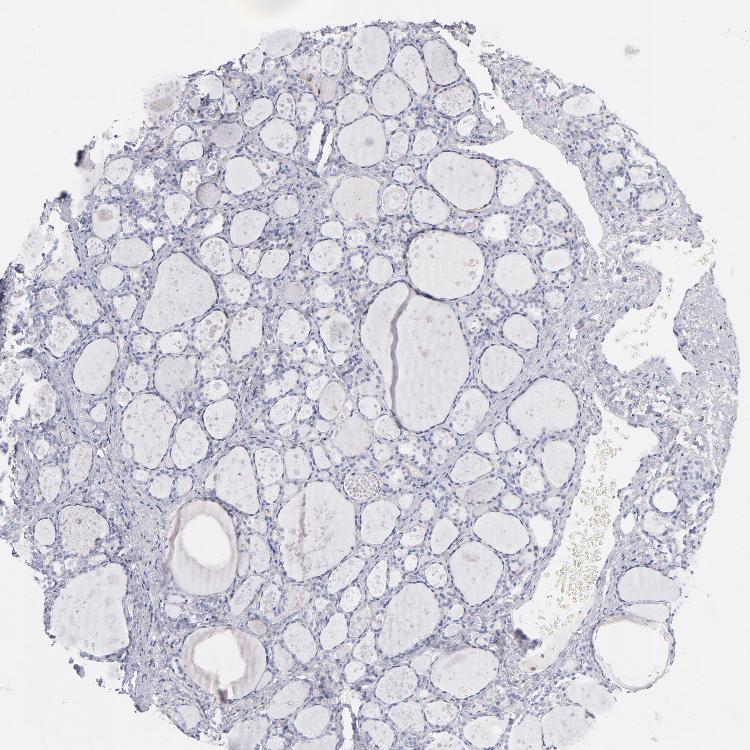

THYROID GLAND - Antibody stainingi

Antibody staining in the annotated cell types in the current human tissue is reported as not detected, low, medium, or high, based on conventional immunohistochemistry profiling in selected tissues. This score is based on the combination of the staining intensity and fraction of stained cells.

Each image is clickable and will lead to virtual microscopy that enables deeper exploration of all samples and also displays staining intensity scores, fraction scores and subcellular localization as well as patient and tissue information for each sample.

Antibody HPA000722Antibody CAB003771

Glandular cells Not detectedNot detected